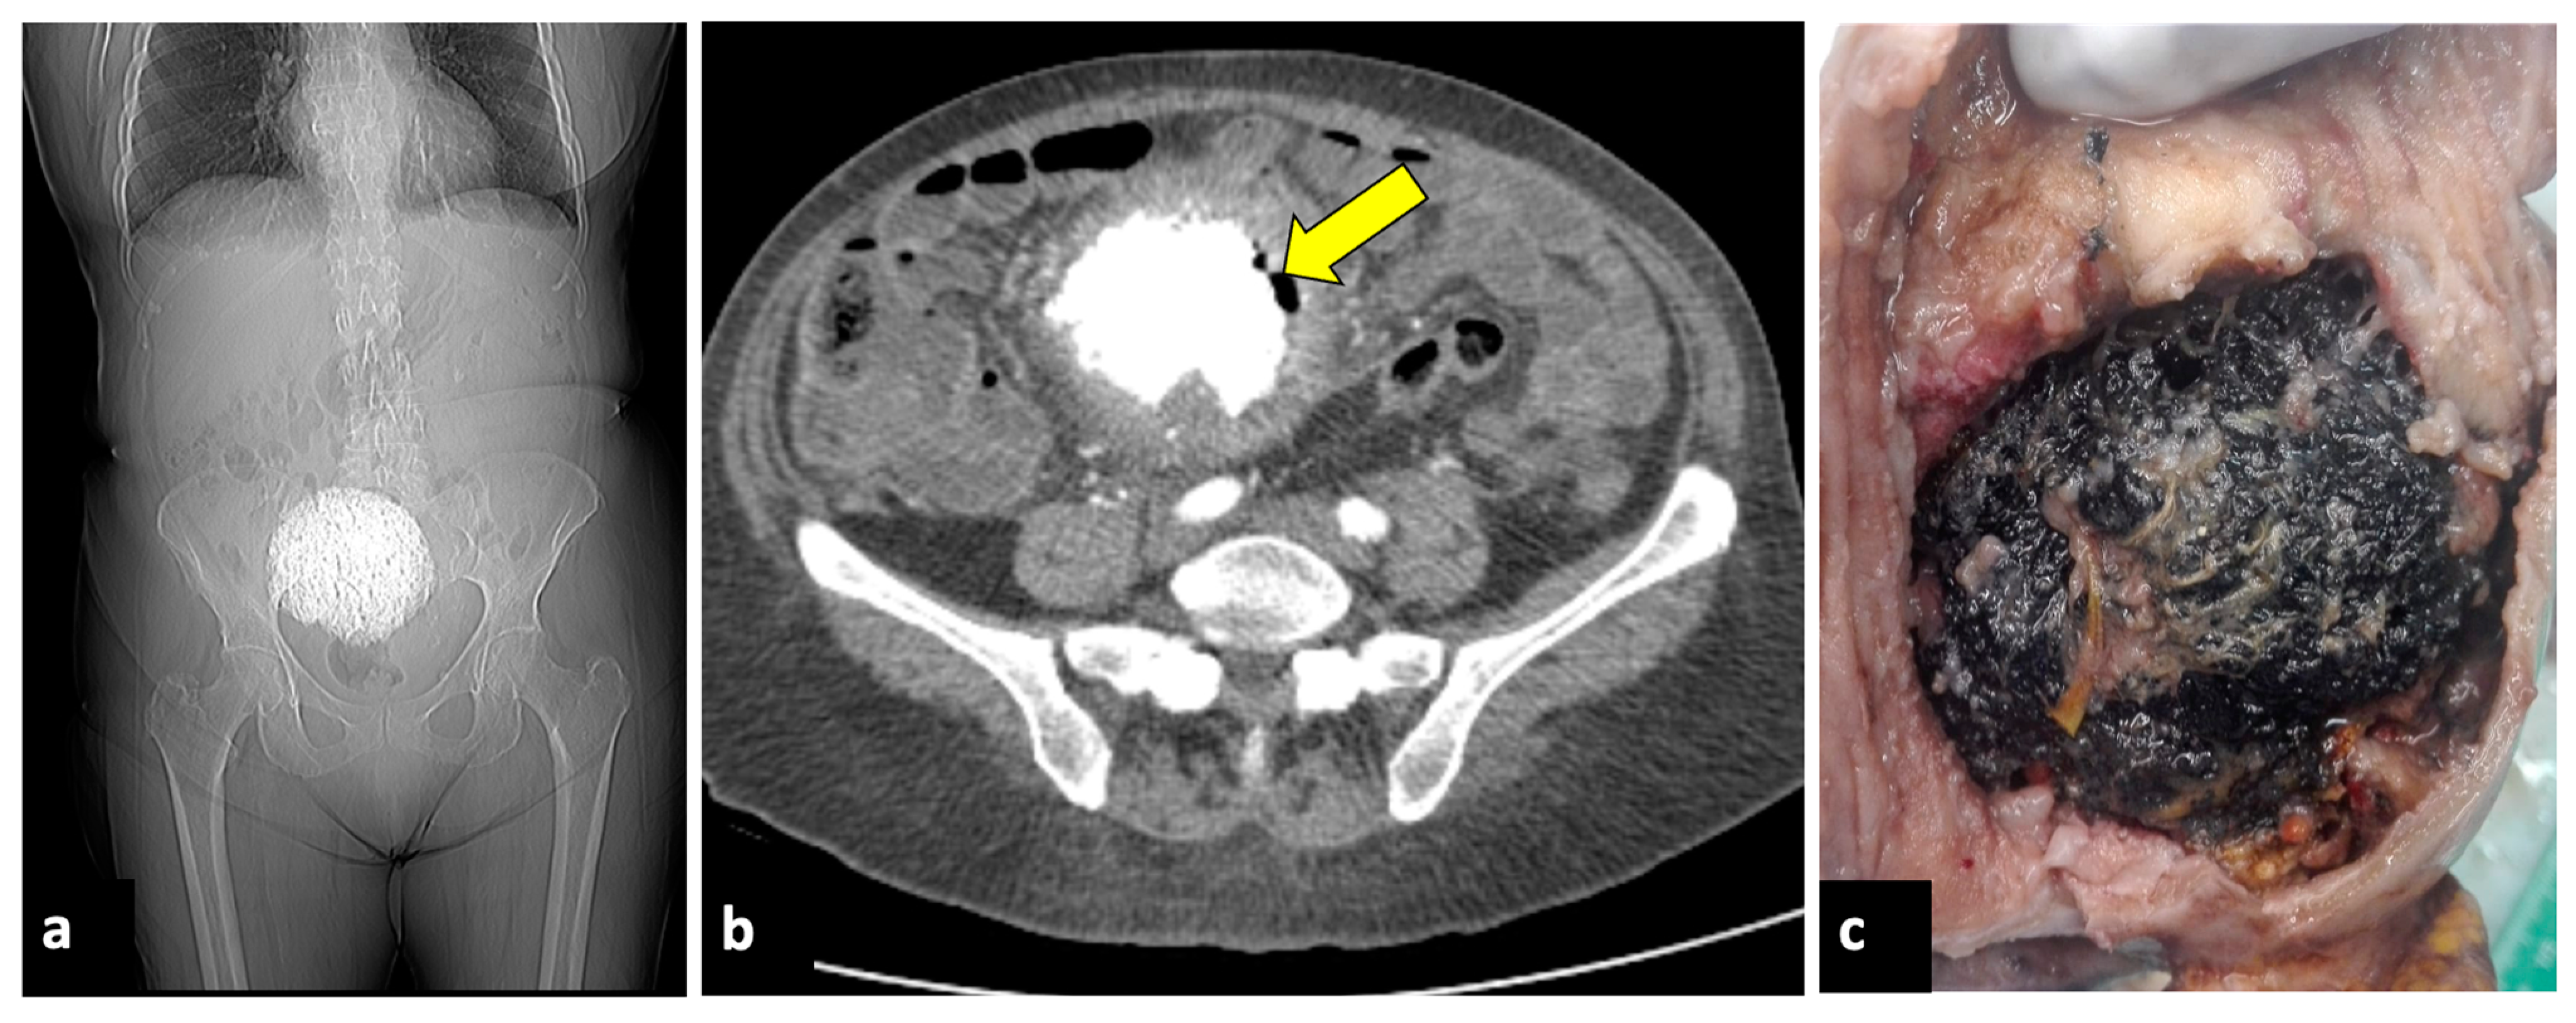

Figure 8.

Pyomyoma in an eighty-year-old woman with a history of diabetes and steroid treatments who presented at the emergency department with fever, leucocytosis, and abdominal cramps for a week. A previous X-ray (a) shows a calcific uterine myoma. Axial CT scan (b) demonstrated the presence of air within the myoma (yellow arrow), eliciting the suspicion of an infected myoma. The patient underwent a hysterectomy (c), and the pathological findings confirmed the diagnosis of pyomyoma.